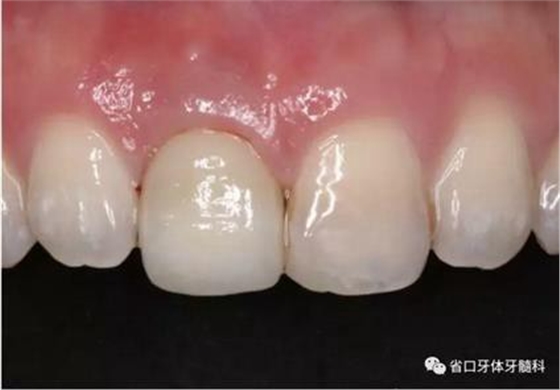

圖21 烤塑臨時冠

圖22 臨時冠就位前袖口檢查

圖23 就位臨時冠

圖24 臨時冠咬合調(diào)整

(2)制備臨時冠:術(shù)后當(dāng)天取模轉(zhuǎn)移,送工廠以Zimmer®多功能 攜帶體為臨時基臺制備臨時修復(fù),獲得舌隆突開孔螺絲固位的烤塑臨時 冠。將其就位于口內(nèi)種植體,調(diào)整正中、前伸及側(cè)方咬合無接觸,加力 10~15N·cm,可見即刻修復(fù)體良好地支持齦緣及牙齦乳頭結(jié)構(gòu)。